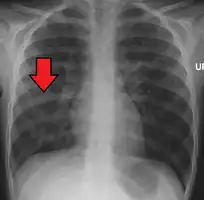

Chest X-ray of a pneumonia caused by influenza and Haemophilus influenzae, with patchy consolidations, mainly in the right upper lobe (arrow)

Pneumonia is usually caused by infection with viruses or bacteria and less commonly by other microorganisms, certain medications or conditions such as autoimmune diseases.[3][4] Risk factors include cystic fibrosis, chronic obstructive pulmonary disease (COPD), sickle cell disease, asthma, diabetes, heart failure, a history of smoking, a poor ability to cough (such as following a stroke), and a weak immune system.[5][7] Diagnosis is often based on symptoms and physical examination.[8] Chest X-rays, blood tests, and culture of the sputum may help confirm the diagnosis.[8] The disease may be classified by where it was acquired, such as community- or hospital-acquired or healthcare-associated pneumonia.[15]